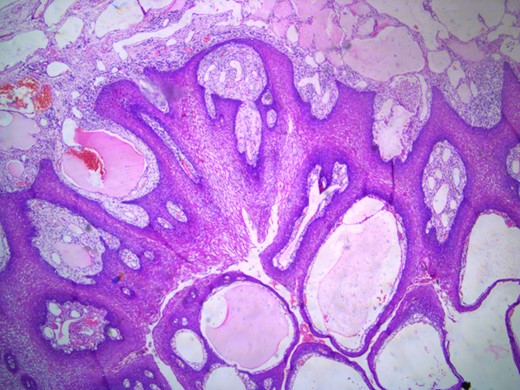

The histopathology report showed mucosa lined by stratified squamous epithelium, with underlying stroma showing dilated vascular channels lined by endothelial cells and containing red blood cells in their lumen confirming the diagnosis of lingual cavernous hemangioma as shown in Figs 5 and 6.

Microscopic appearance of the lingual cavernous hemangioma stained with eosin and hematoxylin at four times magnification.

Microscopic appearance of the lingual cavernous hemangioma stained with eosin and hematoxylin at 10 times magnification.